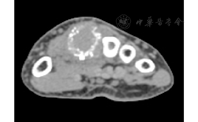

例1 患者女,65岁,因咳嗽咳痰、间断咯血11 d,于2012年12月26日就诊于我院。入院前,胸部CT检查示右上肺阴影,肿瘤性病变可能性大,左下肺感染性病变。PET-CT检查示,右上肺尖端软组织肿块影,伴代谢活性增高,考虑周围性肺癌。入院后,电子支气管镜检查示,双侧支气管黏膜炎症样改变。2013年1月14日行胸腔镜下右上肺叶切除术,术后病理结果示,右上肺腺癌中分化型。术后共行4个周期化疗,为培美曲赛联合奈达铂,末次化疗时间为2013年4月18日。2013年5月16日,开始行肺部病灶术后放疗,每次2 Gy,每周5次,共给予50 Gy。2014年7月,患者出现右手中度肿胀,局部皮肤发红,皮温升高,第二掌骨压痛,屈伸活动受限等症状。放射性核素骨扫描(ECT)检查提示,右手背骨质代谢活跃,性质待查,建议定期复查。2014年7月2日,行右手X线检查示,左手第二掌骨远端呈溶骨性破坏,余未见明显异常。2014年7月3日,右腕关节CT平扫结果示,右手第二掌骨见软组织肿块,骨质破坏,考虑转移(图1);余腕关节诸骨未见明显异常,关节间隙未见异常。手部病灶行穿刺活检,病理结果提示,右手掌骨转移性腺癌(图2)。2014年7月17日,开始对手部骨转移部位行放疗,每次5 Gy,每周5次,共给予50 Gy,同时使用破骨细胞抑制剂治疗。此患者后续在我院继续行放化疗等综合治疗,病情稳定,其总生存时间超过42个月,目前仍在随访中。